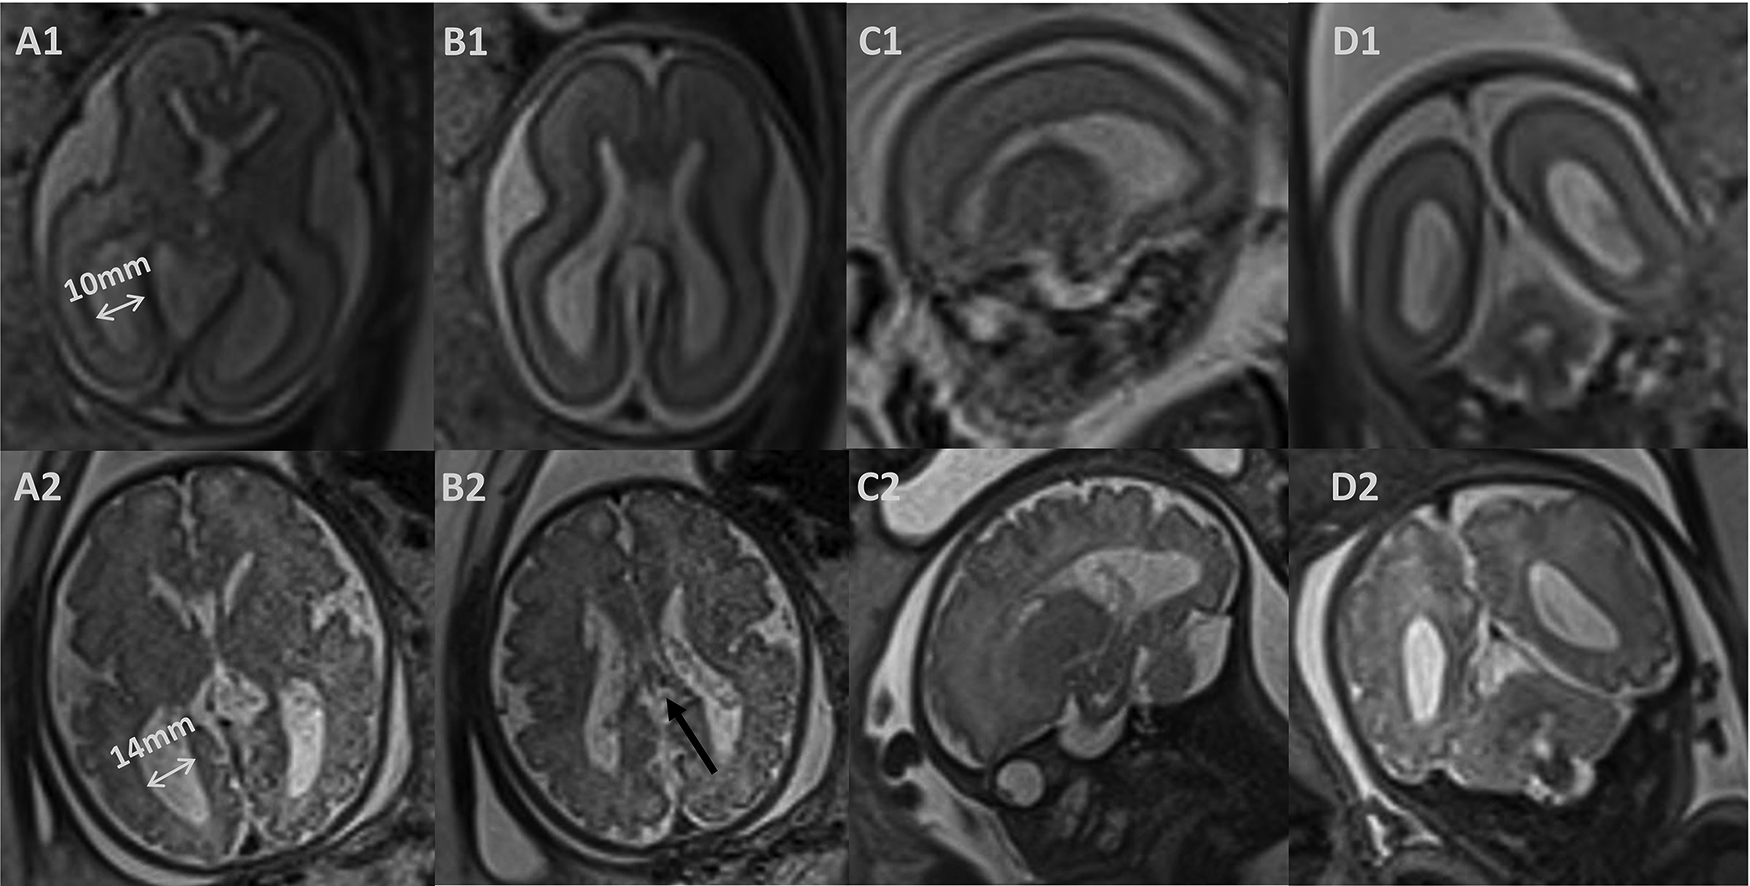

Figure 2

Prenatal magnetic resonance images. (1) T2-weighted image at 25 weeks of gestation. (2) T2-weighted image at 35 weeks of gestation. Axial (A, B) and coronal (D) images showed symmetrically dilated lateral ventricles, and corpus callosum agenesis (black arrow); sagittal (C) images showed abnormal morphology of the right ventricle.

She was delivered naturally at 41 weeks of gestation with a weight of 3470 g and an Apgar score of 10 at both 1 and 5 min. The physical and neurological examinations were normal at birth. Fetal ventriculomegaly was detected at 22 weeks of gestation. An amniocentesis showed a normal karyotype and chromosomal microarray analysis. The TORCH screening test showed a negative result. A prenatal ultrasound had been performed weekly to monitor the fetal ventriculomegaly. The lateral ventricle atrium width was shown to progressively enlarge from 10 mm at 22 weeks to 14 mm at 35 weeks. Furthermore, fetal brain magnetic resonance imaging (MRI) was performed at 25 and 35 weeks, describing symmetrically dilated lateral ventricles, corpus callosum agenesis, and abnormal morphology of the right ventricle (Figure 2). The brain parenchyma volume and morphology were normal. The choroid plexus presented a normal signal intensity on all sequences and there were no signs of intraventricular hemorrhage or plexus cysts. She had an unremarkable familial and personal history.